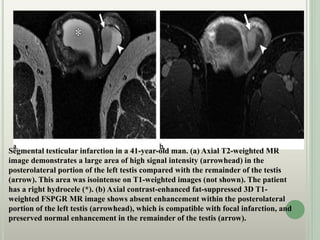

Segmental testicular infarction in a 41-year-old man. (a) Axial T2-weighted MR

image demonstrates a large area of high signal intensity (arrowhead) in the

posterolateral portion of the left testis compared with the remainder of the testis

(arrow). This area was isointense on T1-weighted images (not shown). The patient

has a right hydrocele (*). (b) Axial contrast-enhanced fat-suppressed 3D T1-

weighted FSPGR MR image shows absent enhancement within the posterolateral

portion of the left testis (arrowhead), which is compatible with focal infarction, and

preserved normal enhancement in the remainder of the testis (arrow).